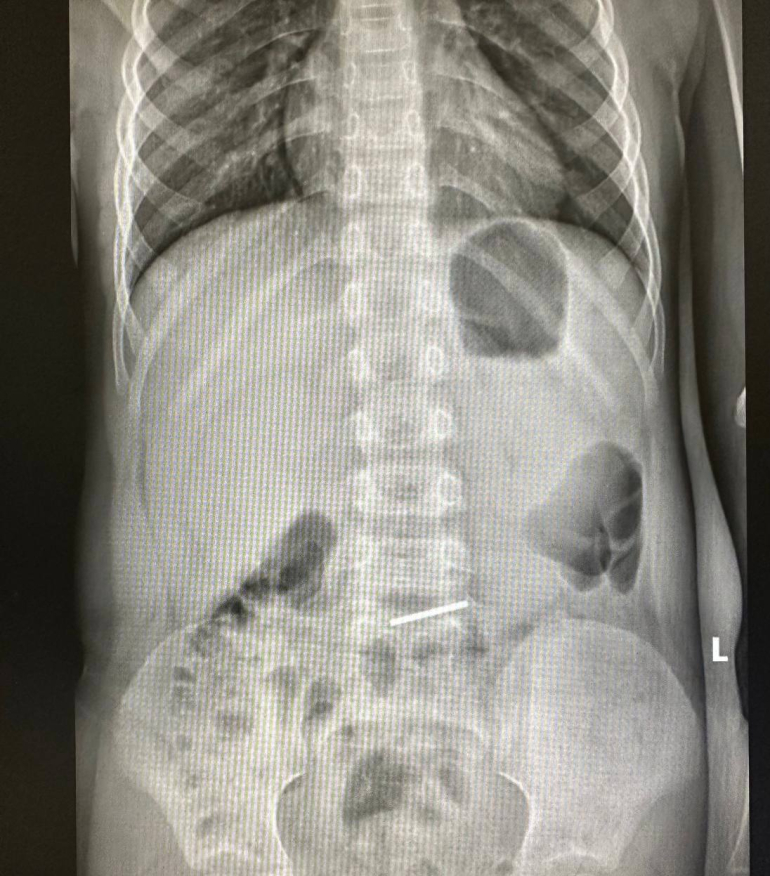

- Мальчик проглотил монетку. При рентгенографии монетка обнаружилась в пищеварительном тракте. Исследование указывало, на то, что монета не двигалась, поэтому в отсроченном порядке ребенку провели эндоскопию и успешно удалили инородное тело, - сообщили врачи.

Инородным телом оказалась киргизская национальная валюта - монета достоинством 10 сом. Сейчас «глотатель» денег чувствует себя хорошо и уже выписан домой.

фото: клиника Рошаля